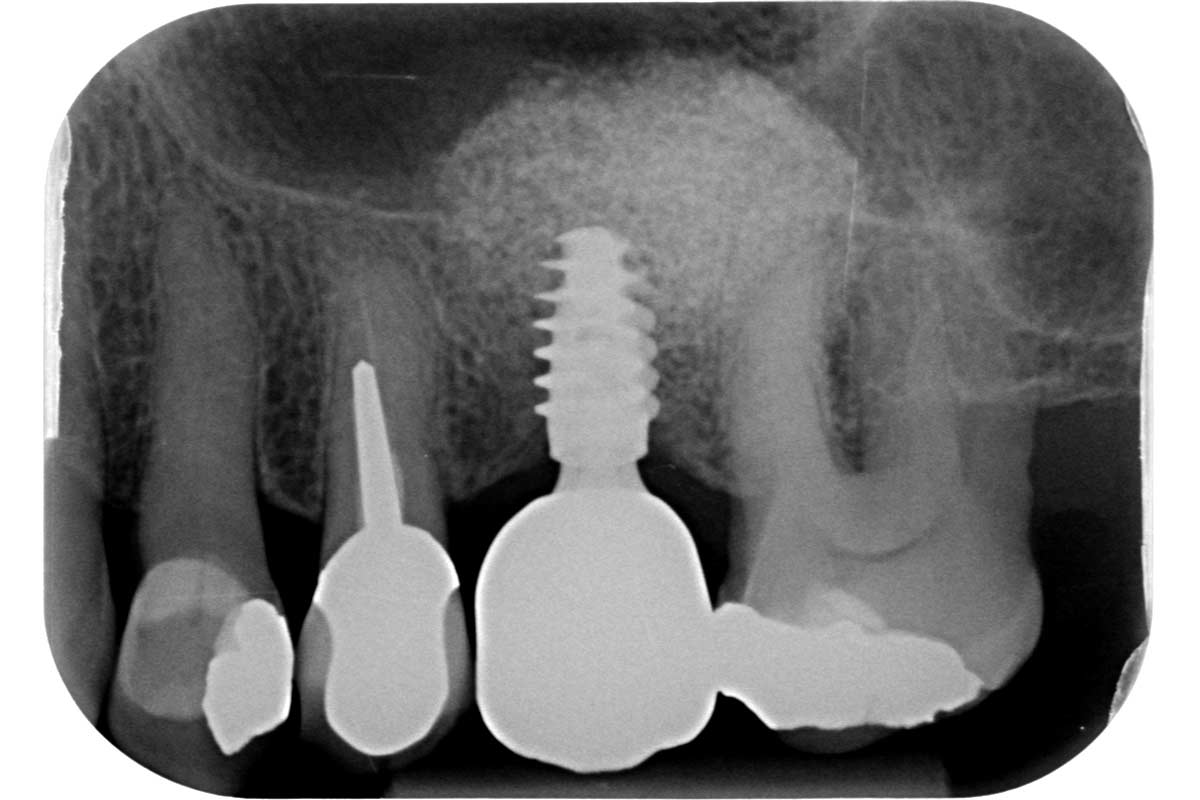

01/35 - Initial x-ray, tooth 25 compromised and to be extractedMaxillary sinus cyst removal using the Crocodile Technique and subsequent lateral sinus lift - Dres. C. Scognamiglio and A. Perucchi